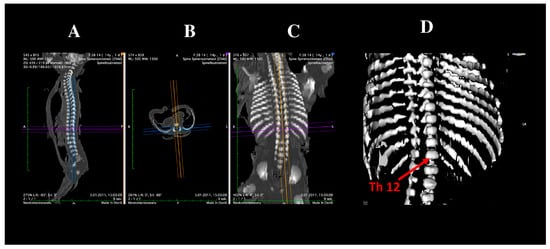

Three-Dimensional, Image-Based Evaluation of the L5 Vertebral Body and Its Ossification Center in Human Fetuses

by Magdalena Grzonkowska, Michał Kułakowski, Karol Elster, Zofia Dzięcioł-Anikiej, Beata Zwierko, Sara Kierońska-Siwak, Magdalena Konieczna-Brazis, Michał Banasiak, Stanisław Orkisz and Mariusz Baumgart

Brain Sci. 2025, 15(11), 1229; https://doi.org/10.3390/brainsci15111229 - 15 Nov 2025

Viewed by 713

Abstract

Objectives: The aim of this study was to characterize the developmental trajectories of the fifth lumbar vertebra in human fetuses by assessing the growth of its vertebral body and ossification center using linear, planar, and volumetric measurements. Methods: A total of 54 [...] Read more.

Objectives: The aim of this study was to characterize the developmental trajectories of the fifth lumbar vertebra in human fetuses by assessing the growth of its vertebral body and ossification center using linear, planar, and volumetric measurements. Methods: A total of 54 human fetuses (26 male and 28 female) aged 17–30 weeks of gestation were examined. Computed tomography, digital image analysis, 3D reconstruction, and statistical modeling were used to quantify morphometric parameters of the L5 vertebral body and its ossification center. Results: All measured parameters demonstrated consistent age-related growth following a linear pattern. No statistically significant differences between sexes were observed in any measured diameter of the L5 vertebra or its ossification center within the examined gestational age range. Conclusions: The normative morphometric data and growth curves obtained for the L5 vertebra and its ossification center provide age-specific reference values that may aid in prenatal diagnostics. These findings can support clinicians in estimating gestational age, assessing vertebral development on ultrasound, and detecting congenital spinal anomalies and skeletal dysplasias at an early stage. Further multicenter studies including a broader gestational age range are warranted to strengthen the generalizability and clinical applicability of these results. Full article

Show Figures